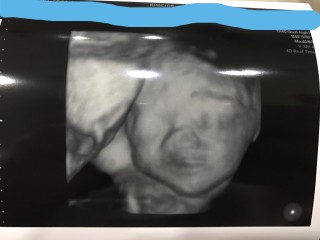

初めての3D.4Dエコーしました! まだ週数が若いからやせ細って見えるとのことでしたが、顔つきや手足を確認できて夫と喜びました。 奇跡的にこちらを向いて手を振ってくれてるポーズをしてくれるサービス精神旺盛の我が子に笑顔がこぼれました!

1ヶ月ぶりの検診♡ 長男の時にもやってもらった念願の4D! お顔がはっきり見えて完全に旦那似であることが分かりました(^^) 前回の検診で90%女の子と言われていましたが 女の子確定で大丈夫と言われ早速必要最低限のお洋服を買ってきました♪ スタイは現在手作り中です♡ 次の検診は2週間後! それまで待ち遠しいです(^^)